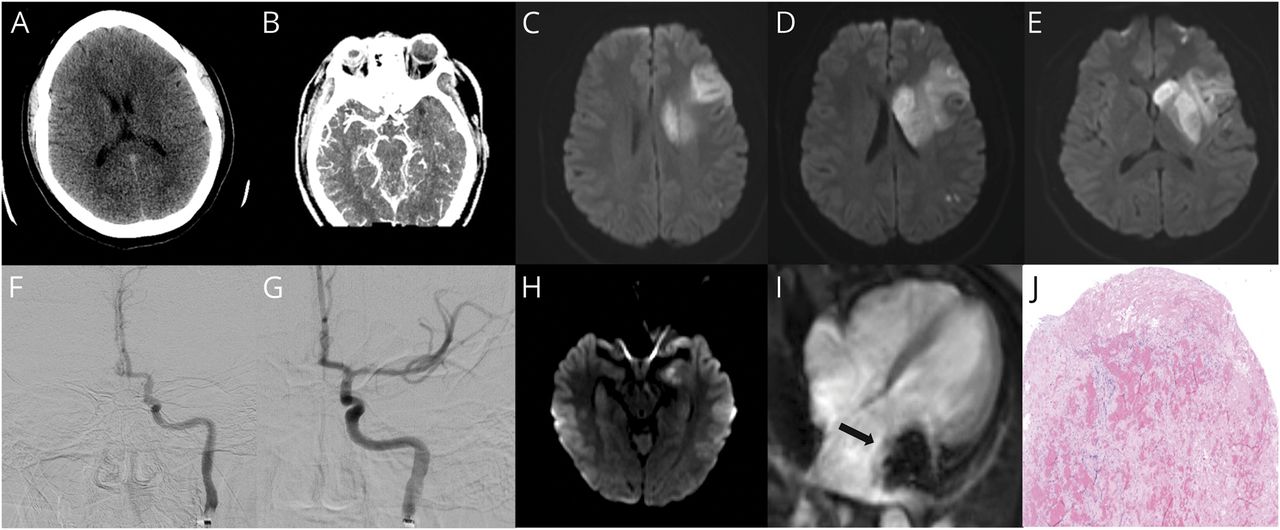

(一)最初的头部CT。(B) CT血管造影显示左大脑中动脉(MCA)领土大血管闭塞。(汉英)Prethrombectomy diffusion-weighted MRI显示限制在左MCA领土。(F) Prethrombectomy血管造影显示填充受损左侧大脑中动脉的起源。(G) Post-thrombectomy成像显示分辨率的流在左侧大脑中动脉。(H) Post-thrombectomy MRI的第七天住院显示左侧中脑的新扩散限制。(我)心脏MRI显示心房粘液瘤在左心房(箭头所指)。(J)切除粘液瘤组织的组织学与表面的纤维蛋白血栓(比例尺和单元不可用)。

CT血管造影显示闭塞的左supraclinoid颈内动脉和左左M1段轻度collateralization M2段(图B)。Diffusion-weighted MRI显示广泛的限制在左MCA领土包括相对应的左尾状核头和豆状核梗塞(图中,汉英)。最近试验(如血管内治疗小核心和近端闭塞缺血性中风(逃跑),延长溶栓时间紧急的神经赤字:动脉内的(扩展IA)和多中心随机ClinicalTrialof血管内治疗急性缺血性中风在荷兰[清洁先生])表明,在大型动脉遮挡,机械血栓切除术的病人与改善功能结果。1自描述的病人目前的情况有一个大血管闭塞,6小时内出现症状,她接受了机械血栓切除术切除左M1阻塞(图F和G)的合成在脑梗死溶栓得分3。她有一个很好的应对血栓切除术,以最小残余失语症检查和一个署10血栓切除术后约24小时。她开始每天阿司匹林和他汀类药物治疗。

可能在年轻人中风机制包括cardioembolism,镰状细胞性贫血,解剖,性烟雾,血管炎,药物滥用,hypercoagulable州,和neurogenetic紊乱。2作为上述病人,中风引起的一个经胸廓的超声心动图,演示了一个大型(> 5厘米)质量在二尖瓣脱垂的左心房进入左心室在舒张。后续心脏MRI显示分成小叶的无定形4.9×2.4×2.5厘米移动左心房与左心室壁附件质量不如立即左心房附件(图,我)。这些心房粘液瘤的影像学检查提出了怀疑,这被认为造成颅内栓子造成病人的报告。进一步的验血结果显示低密度脂蛋白水平的81和5.1的糖化血红蛋白。抗凝血酶III的病人hypercoagulation检查返回的89年,98年总蛋白S,游离蛋白S 60,和蛋白C的110,都是负面的狼疮抗凝及凝血酶原基因突变。

最近全身溶栓疗法立即手术切除心房粘液瘤的风险由于出血并发症的可能性。然而,第七天住院,病人最近诊断为复视。她进行了重复MRI,展示了一个新的在左侧中脑梗塞(图中,H)。鉴于这种中风复发和预防栓塞事件的三分之一的目标,决定继续心脏肿瘤切除手术。术中发现显示,左心房的肿瘤占80%。质量的起源的起源被发现在左侧优越的伪劣肺静脉。由于其规模,以零散的方式切除。严重,切除骨料的脆性、semitranslucent tan-red组织碎片7×6×1厘米。的粘液瘤由片状出血,焦含铁血黄素沉积和表面的纤维蛋白血栓(图中,J)。发达没有病人手术后的并发症和没有复发性缺血性事件。当看到在中风临床随访2个月,她发现恢复良好,署的4。